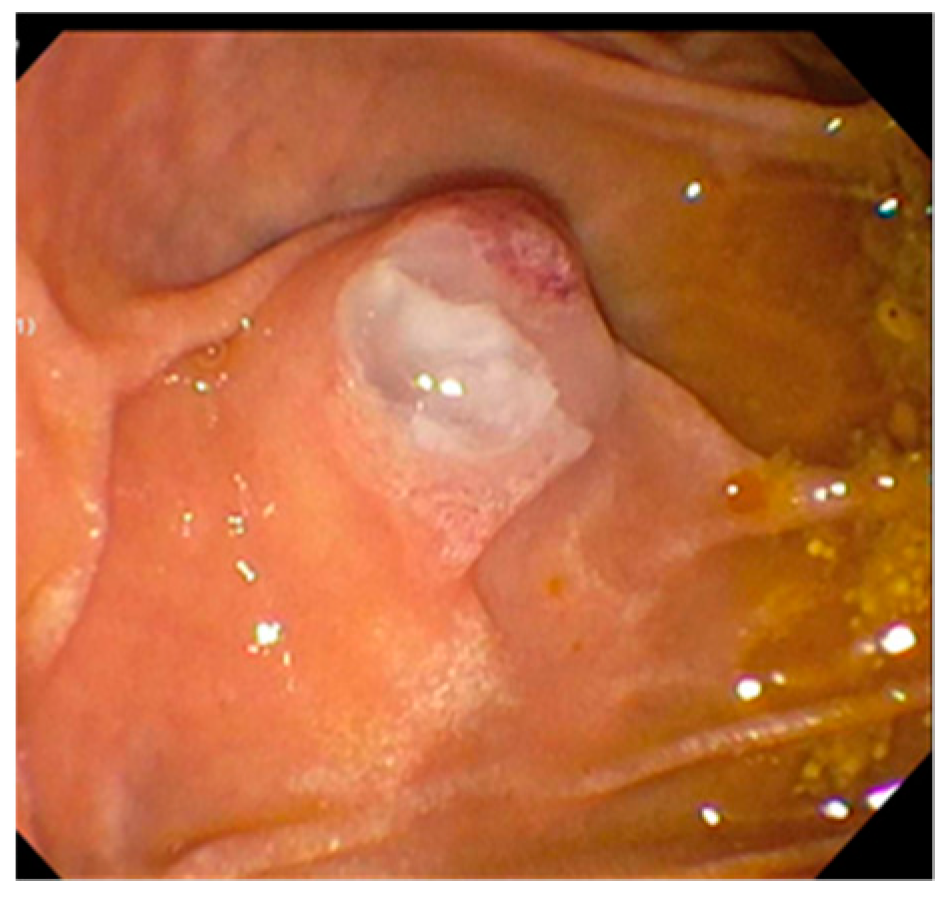

3. Indeterminate Biliary Strictures

| Evaluation of strictures |

| Visually guided biopsy |